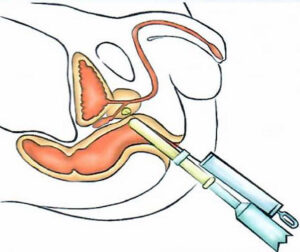

ESPLORAZIONE RETTALE

ESPLORAZIONE RETTALE

L'esplorazione rettale è una vecchia, ma sempre consigliabile, manovra diagnostica che dà informazioni preziose sullo stato, le dimensioni e sui rapporti della prostata con gli organi vicini.

E' possibile, con questo semplice atto, diagnosticare delle prostate ingrossate in modo benigno, infiammate o anche tumorali.

Oggi, di fronte a valori del PSA superiori a 4 pur in presenza di un'esplorazione rettale negativa, solitamente si deve effettuare un'ecografia transrettale con biopsie multiple.

Tale esame viene condotto esclusivamente dallo specialista urologo.